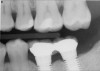

Figure 12  Horizontal spacing needed between the natural tooth and the implants and between the adjacent implants.

Figure 12